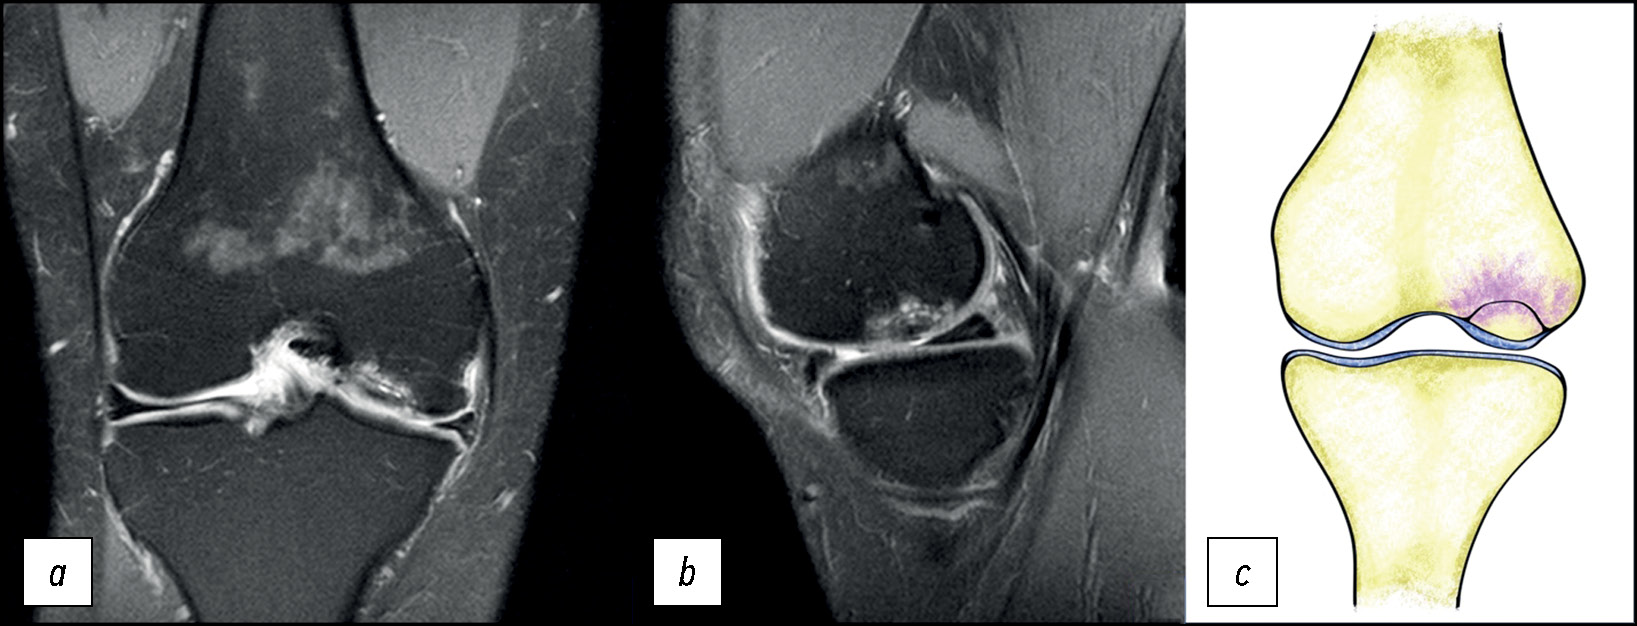

На выполненных рентгенограммах патологии не выявлено. Пациент наблюдался в клинике по месту жительства с диагнозом «остеоартрит коленного сустава». В связи с неэффективностью применения нестероидных противовоспалительных препаратов выполнил МРТ-исследование, на котором выявлен отёк костной ткани в области наружного мыщелка бедренной кости (рис. 1), плавно переходящий на внутренний мыщелок.

Рис. 1. МР-томограммы коленного сустава: а, b — изображение в T2w-STIR режиме, с — изображение в режиме Т1 в корональной проекции, и графическое изображение остеонекроза мыщелка в сагиттальной проекции (d).

Fig. 1. MR images of the knee: а, b — T2-weighted short-tau inversion recovery (T2w-STIR), с — T1-weighted sequences in the coronal projection and a graphic image of an osteonecrosis (d).

Состояние расценено как идиопатический асептический некроз наружного мыщелка бедренной кости I стадии по классификации ARCO (остеонекроз) (M87.0) [8].

Особенности отёка костной ткани: достаточно равномерный, без каких-либо линий и включений, распространяется на большую часть мыщелка. Гиалиновый хрящ не вовлечён в патологический процесс, имеет ровную поверхность без деформации, что характерно для начальной стадии асептического некроза [9].